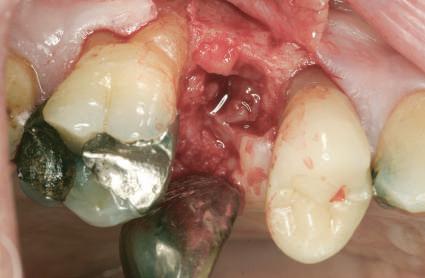

Când implanturile la nivel osos se plasează cu bizou orizontal şi hexagon intern, forma componentelor restauratoare necesită "spaţiu liber" pentru a crea forma rădăcinii şi un profil de

emergenţă adecvat asigurării aspectului natural al dintelui.

Atunci când conform obiectivului, implanturile se plasează la nivelul sau uşor sub nivelul osului şi la cel puţin 2mm de peretele vestibular, există ţesut moale generos şi spaţiu vertical amplu pentru ca tehnicianul să dezvolte contururile de emergenţă ce îndeplinesc criteriile ce urmează a fi discutate în prezentul articol.

Dacă însă implanturile sunt plasate prea vestibular sau prea superficial, componentele nu permit un design adecvat al bontului, pentru că plasarea marginii este limitată iar conturul facial şi proximal poate fi compromis (fig. 1, 2).